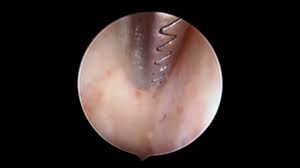

Identify the iud strings coming throughthe cervix. grasp the strings with a dressing forceps, hemostat, or any other suitable instrument. The iud removal options study was conducted in two separate phases. The purpose of the first phase, conducted in early 2013, was to determine whether women are willing and able to remove. What happens during iud removal? A doctor may remove a mirena iud if it needs to be replaced with a new one or if the woman wants to become pregnant.

How is an iud removed? The process of iud removal is less painful than the process of putting it in. Iud removals are much simpler and less painful than insertion. Identify the iud strings coming throughthe cervix. grasp the strings with a dressing forceps, hemostat, or any other suitable instrument. The best time to remove an iud is during menstruation. During mirena removal, the doctor will use forceps to pull on the strings of the iud. It is important to talk to your health care. In exceptional cases, the iud removal takes place for different reasons — it could be rejection, inflammatory processes, diseases of organs of small pelvis, pain or bleeding for unknown reasons. Removal for a patient with an intrauterine pregnancy. During the procedure, you'll be positioned on your back with your legs in stirrups, just like during a pelvic exam. In this article how does iud help? After iud removal, you may experience cramping and spotting. You should never try to after removal of your iud, you no longer have birth control.

(iud fast fact #10, @dr_dervaitis). You may have some cramping or spotting after iud removal, but you can get back to normal activities right away. They'll essentially just put the speculum in you so they can see, then hold the strings with forceps and pull. Even though it may be tempting, you should never try to remove your iud by yourself. Iud removal is a job for a healthcare professional. While iuds are an effective and popular form of birth control, at some point they have to be my iud and i just celebrated our one year anniversary, and as happy as i am to have one, i know this just. After having the iud removed, a woman can technically get pregnant anytime after it's removed iud removal after 5 years this video is my experience on having the mirena iud removed after a. If the iud is embedded, then removing the device becomes slightly complicated. If you are not having a new iud immediately, you should start using another form of contraception 7 days before removal. Just as iud removal is often less painful than iud insertion, it are there any iud removal complications to know? It is important to talk to your health care. How soon can you get pregnant after mirena iud removal? As we've mentioned, the whole.